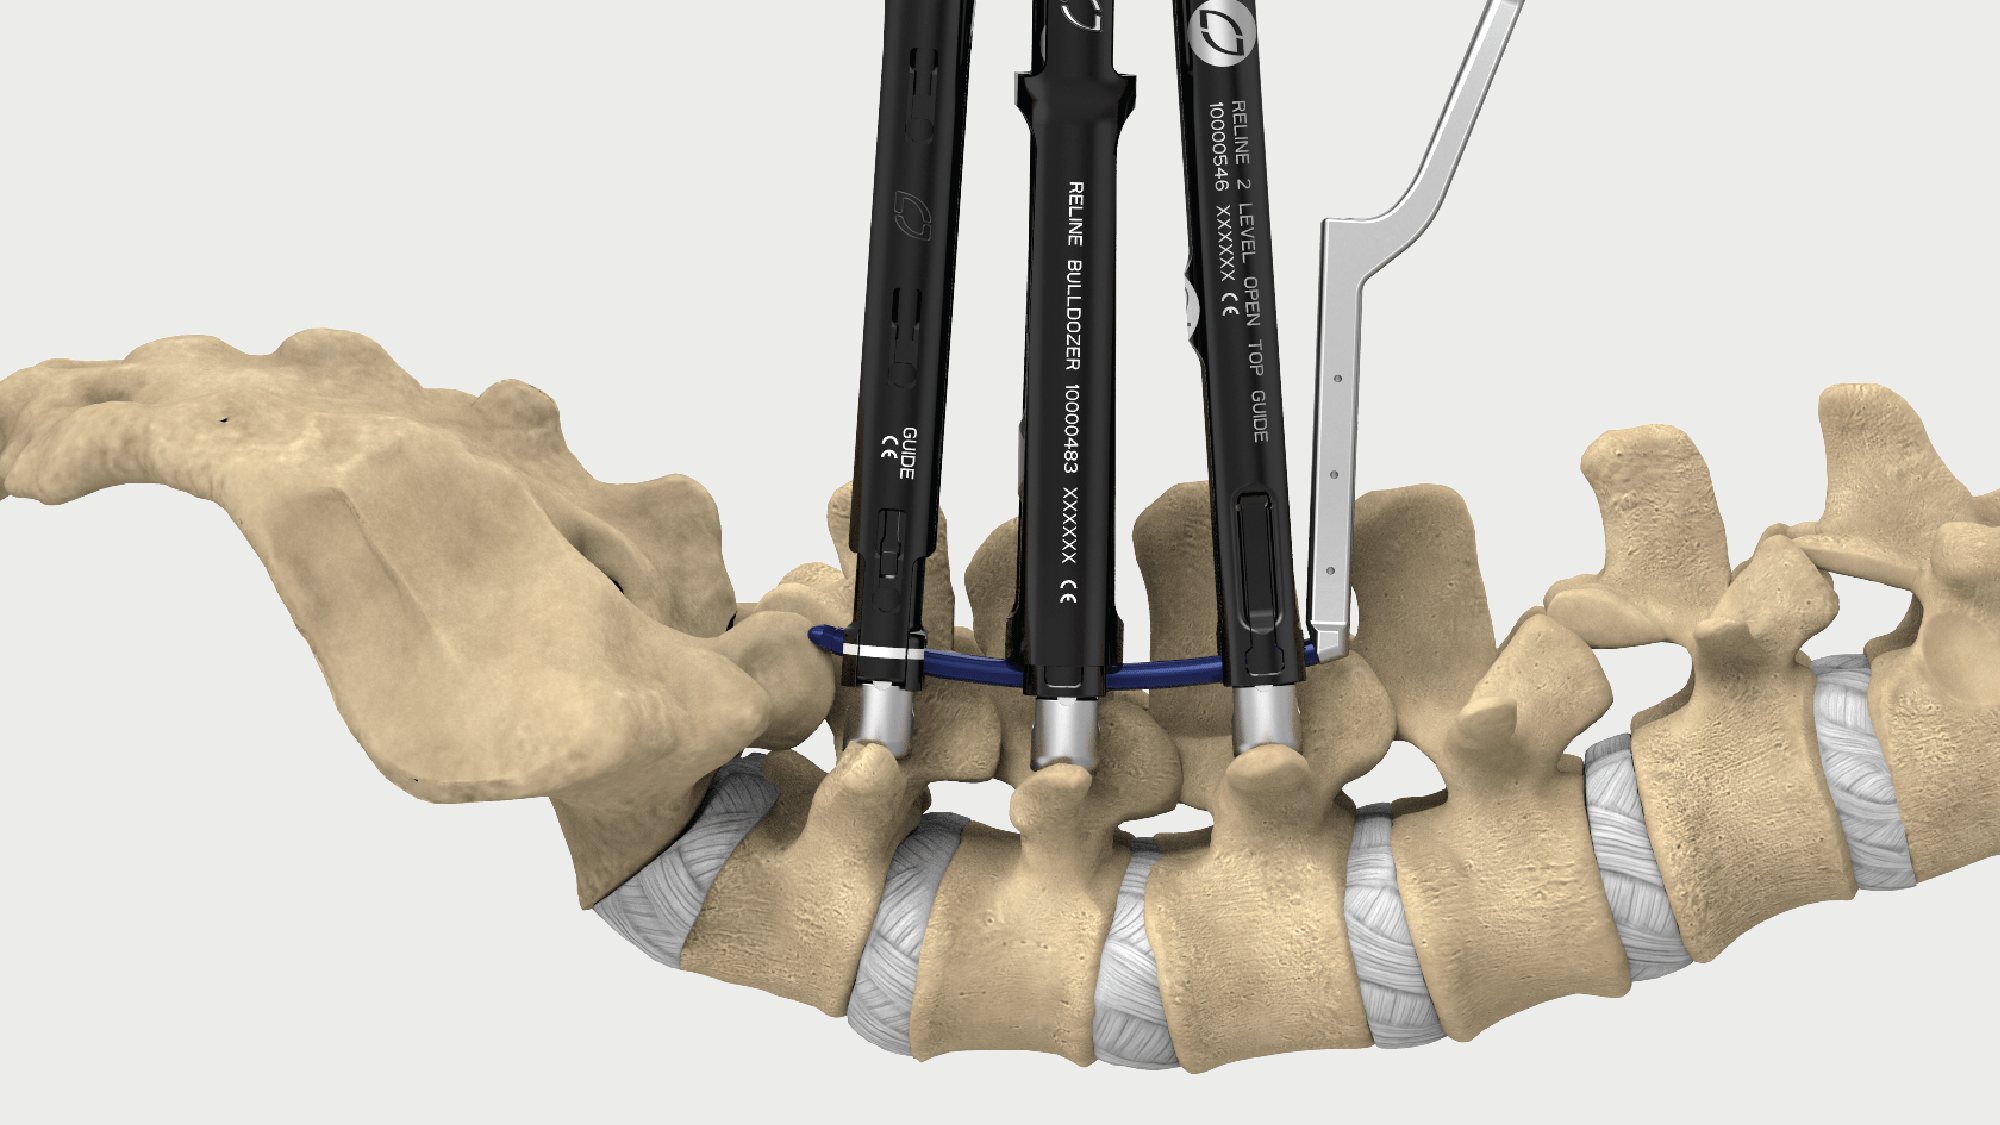

NUVASIVE XLIF SURGICAL TECHNIQUE PDF Pain After Xlif Surgery Pseudoarthrosis may go undetected or lead to a. Learn what psoas muscle pain is, how it affects your recovery after xlif surgery, and how to alleviate it with rest, ice, stretching,. In general, xlif surgical recovery may include: Learn what to expect after an extreme lateral interbody fusion (xlif) surgery, including pain management, activity limitations. Postoperative care for spinal fusion. Pain After Xlif Surgery.

eXtreme Lateral Interbody Fusion (XLIF) Nuvasive Surgical Technique OrthOracle Pain After Xlif Surgery Pain is likely to continue to decrease gradually, but some patients continue to have pain 3 to 6 months after surgery. Pseudoarthrosis may go undetected or lead to a. Pain and bruising at the incision sites after surgery, which can be controlled with oral pain medication and eventually. Postoperative care for spinal fusion surgery. Learn what psoas muscle pain is,. Pain After Xlif Surgery.

From www.nuvasive.com

Featured Case X360 featuring Modulus XLIF, Reline and LessRay NuVasive Pain After Xlif Surgery Learn what psoas muscle pain is, how it affects your recovery after xlif surgery, and how to alleviate it with rest, ice, stretching,. Postoperative care for spinal fusion surgery. Pain is likely to continue to decrease gradually, but some patients continue to have pain 3 to 6 months after surgery. Learn what to expect after an extreme lateral interbody fusion. Pain After Xlif Surgery.